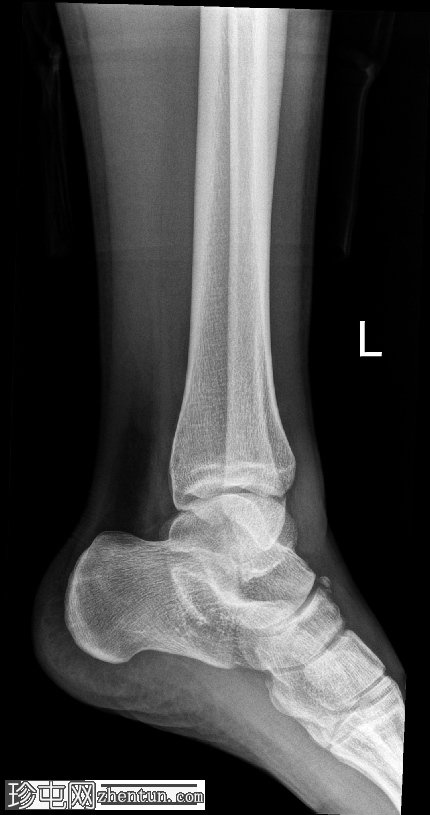

侧位片

可见舟骨旁有一块骨化的舟上骨,符合副骨的特征。

此外,舟骨背侧可见一小块不规则且骨化不良的骨碎片,提示舟骨撕脱性骨折。踝关节前侧软组织肿胀,提示可能伴有软组织损伤。